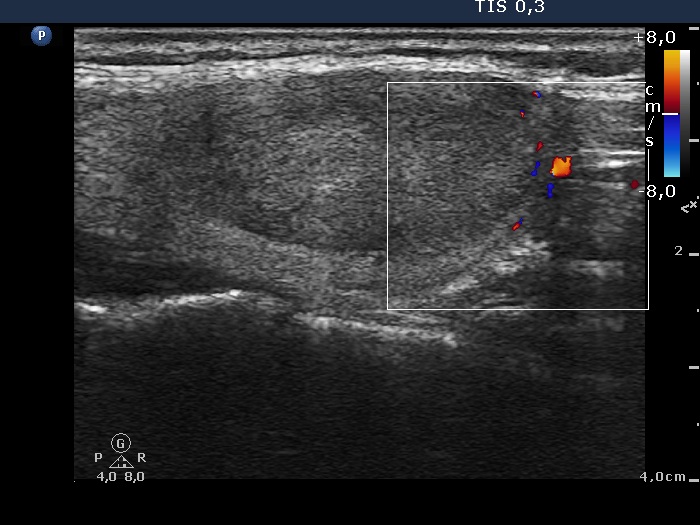

Ultrasonography: the thyroids were echonormal. There was a moderately hypoechogenic-echonormal nodule in the left lobe. The nodule displayed a halo sign but neither perinodular nor intranodular blood flow.

The presence of halo in the absence of unequivocal perinodular blood flow is a very rare situation in the case of a follicular tumor.